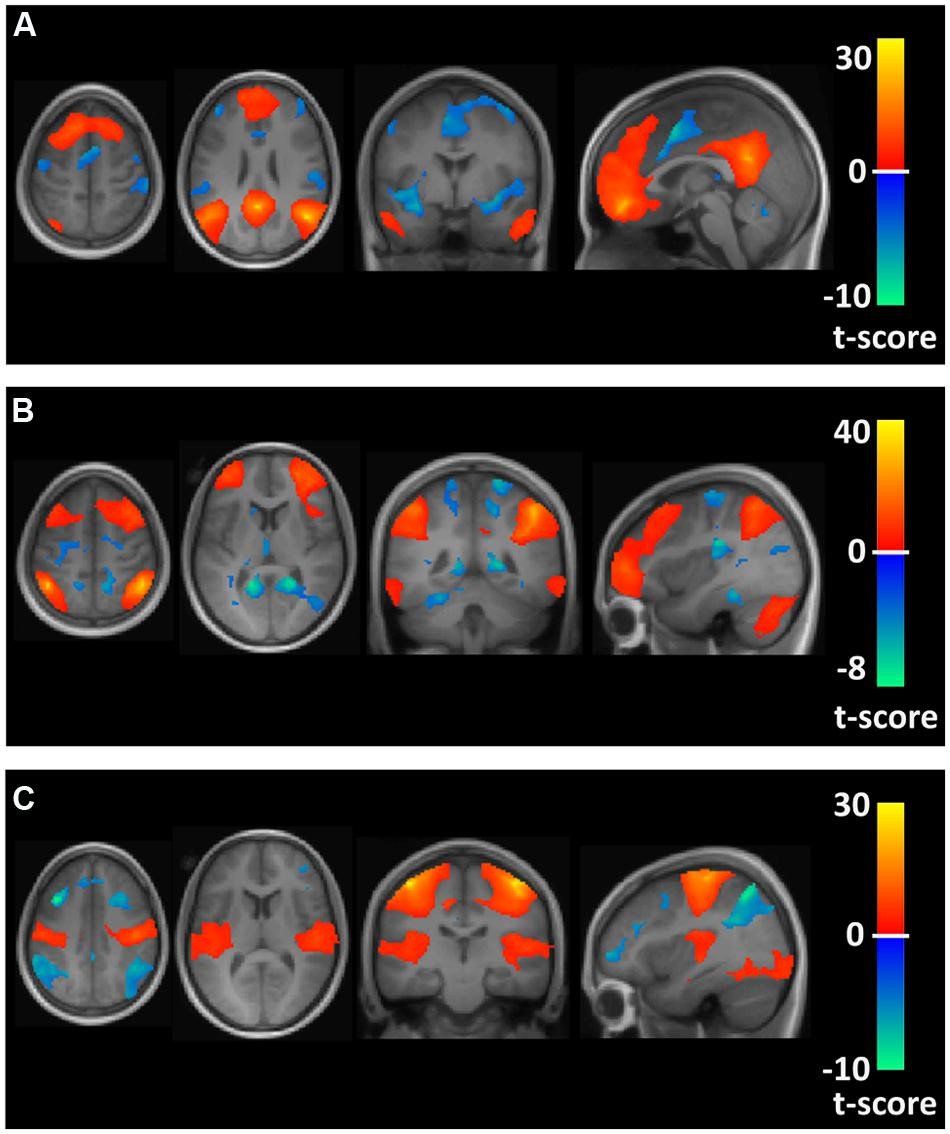

Humans use much more than 10% of their brains. Through brain imaging technique, called functional magnetic resonance imaging (fMRI), researchers show that we use most of our brains to perform the simplest tasks. #MythDebunked #BrainFunctions #HumanBrain

Register now for this #PreclinicalImaging webinar on Sep. 26th: Mapping #brainfunctions by #fMRI with stimulus driven BOLD and MEMRI techniques. okt.to/HTl0bu #brainimaging @UniFAU

Register now for this #PreclinicalImaging webinar on Sep. 26th: Mapping #brainfunctions by #fMRI with stimulus driven BOLD and MEMRI techniques. okt.to/HTl0bu #brainimaging @UniFAU